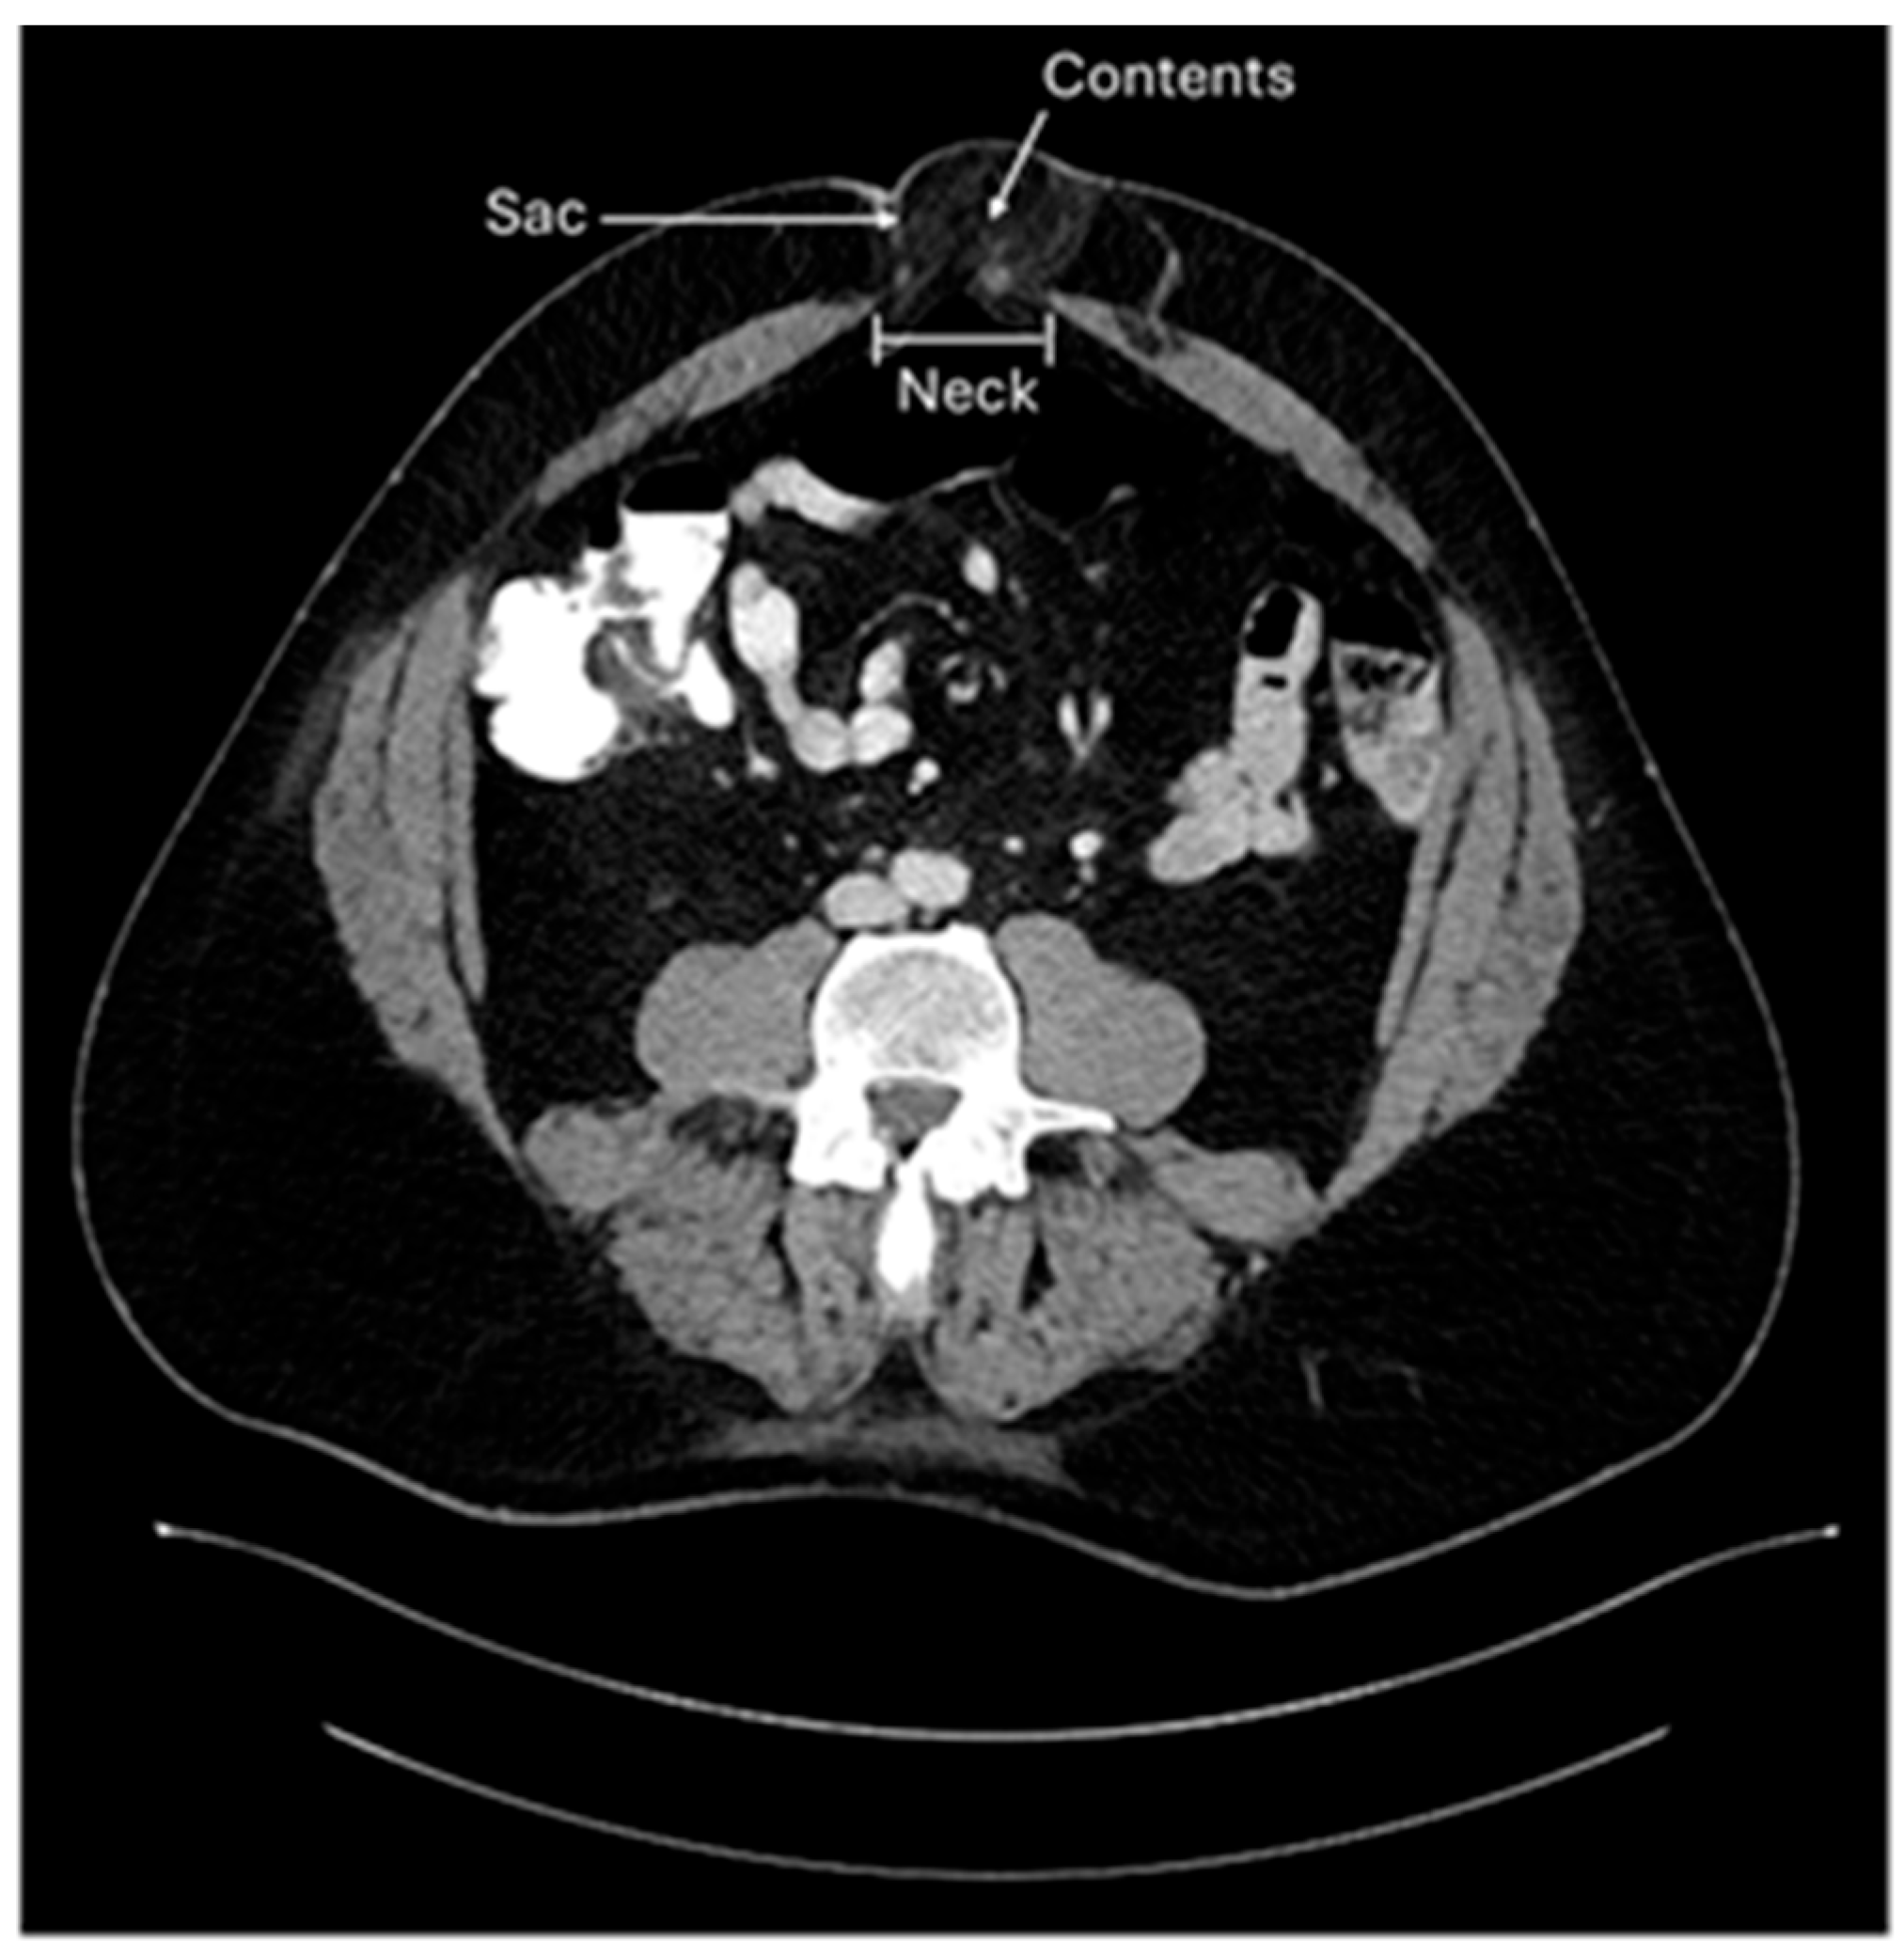

A hernia occurs in an area of the body that is devoid of striated muscle. Structures normally contained within a normal compartment protrude through a “rupture” (Latin for hernia) into a non-anatomic cavity. Three components are characteristic of hernias: the neck is the rupture of the fascia that allows the protrusion of hernia contents; the hernia sac, a lining of peritoneum through the defect; and the hernia contents, which are any structures contained within the hernia sac (Figure 1) [1].

Figure 1. Umbilical hernia with three components: neck, sac, and contents.